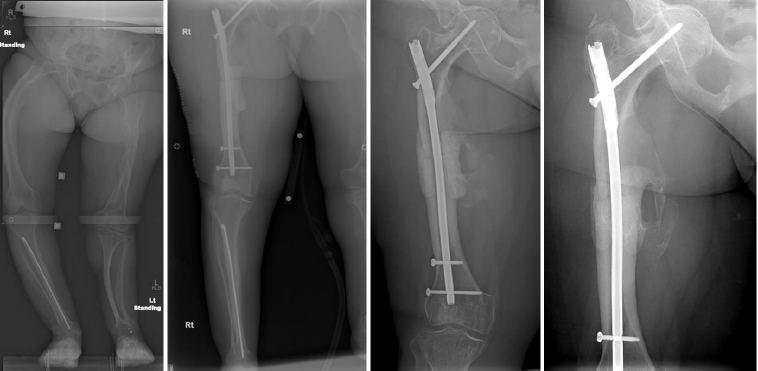

Complications occurred in 5 patients with tibial DC, including 3 cases of hardware removal due to symptomatic prominent interlocking screws and 1 case of delayed union. Complications arose in 4 patients with femoral DC, including 3 cases of nonunion, 1 case of hardware removal due to prominent screws, and 1 case of nonunion and infection (Table 1). There were no cases of peroneal nerve palsy or compartment syndrome. All patients achieved eventual clinical and radiographic union. Pre- and postoperative radiographs of 4 cases are included to highlight the variation in presentation and operative site (Figs. 4-7).

From left to right: Preoperatively, immediately postoperatively, 5 months postoperatively, and 5 years postoperatively (patient #7).